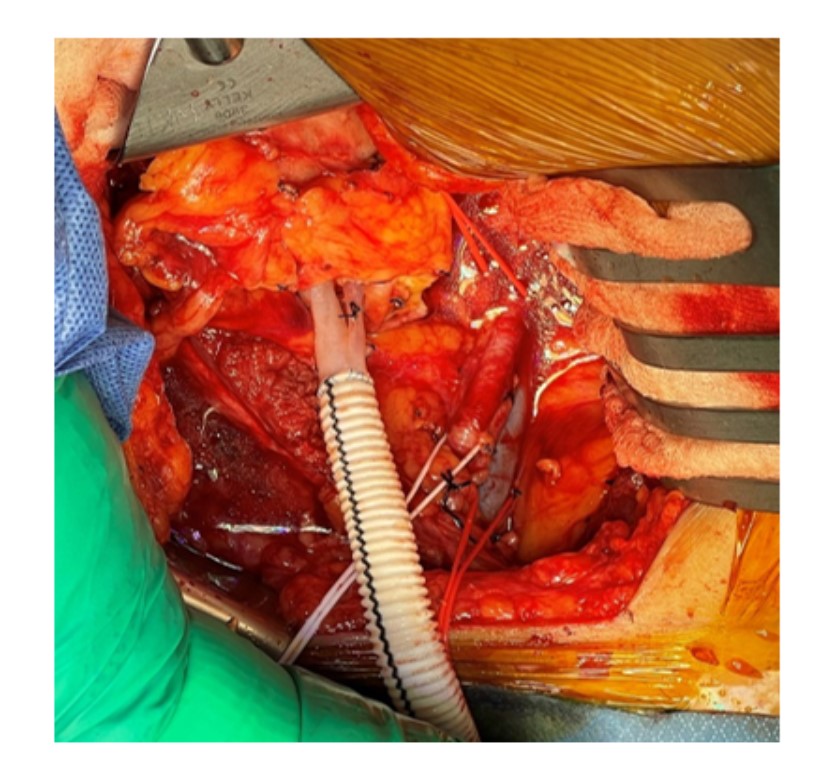

Summary: Our patient is a 51-year-old female, diagnosed case of End Stage Renal Disease secondary to Adult Polycystic Kidney disease underwent renal allograft transplantation using a left allograft kidney obtained via laparoscopic donor nephrectomy with a single cuffed double artery and a short single renal vein. Renal vein extension was done using a polyester vascular graft to provide tension-free vascular anastomosis and proper renal graft placement. Immediate graft function and stable allograft function post-transplantation were observed.

Conclusion: Renal vein extension using polyester vascular graft is a feasible and safe technique to address difficulties during vascular anastomosis while reducing the risks of delayed graft function and other associated vascular complications.